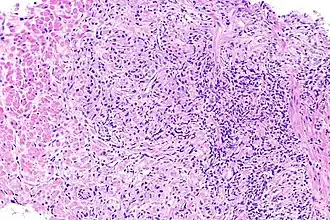

Биопсия предстательной железы при остром простатите не показана, так как может способствовать распространению инфекции или дополнительному инфицированию простаты ещё одним типом микроорганизмов. Кроме того, биопсия предстательной железы как диагностическая процедура при остром простатите просто не требуется, поскольку характерные клинические признаки и симптомы, а также данные пальцевого исследования предстательной железы, анализов крови, мочи и мазков из мочеиспускательного канала обычно позволяют поставить правильный диагноз и без биопсии. Гистологическим коррелятом острого простатита является нейтрофильная инфильтрация ткани предстательной железы.